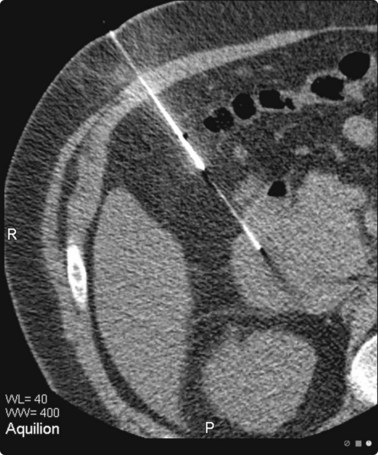

image

Fig. 3.4 Fine needle biopsy of a suspicious tumour mass in a small breast

Continuous visualization of the needle tip prevents the risk of pneumothorax.

Many operators prefer US guidance for its speed, flexibility and real-time facilities. The patient is also able to lie comfortably during the procedure. The method is limited by the type of lesion; many microcalcifications are not visible on ultrasound examination. There is also the slight risk of pleural puncture or pneumothorax if used by inexperienced operators. The needle should run parallel to the chest wall and never be introduced perpendicular to the ribcage (see Fig. 3.4). By positioning the patient and compressing the breast, the depth of the lesion can be reduced. Breast lesions often require multiple sampling, typically best achieved using ultrasound guidance (Fig. 3.5).